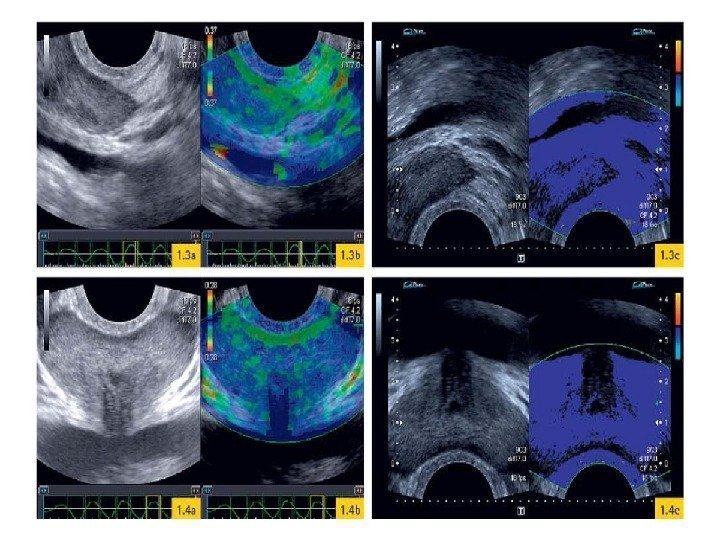

Эластография Метод основан на том, что ткань злокачественной опухоли является значительно более плотной, чем нормальная. С помощью эластографии производится измерение эластических свойств тканей железы во время компрессии датчиком и их представление на экране в виде зон различной цветовой окраски – это качественная оценка. Так же у некоторых фирм-производителей ультразвуковой аппаратуры имеются аппараты с количественной оценкой эластичности опухолевой ткани в процентном отношении к здоровой.